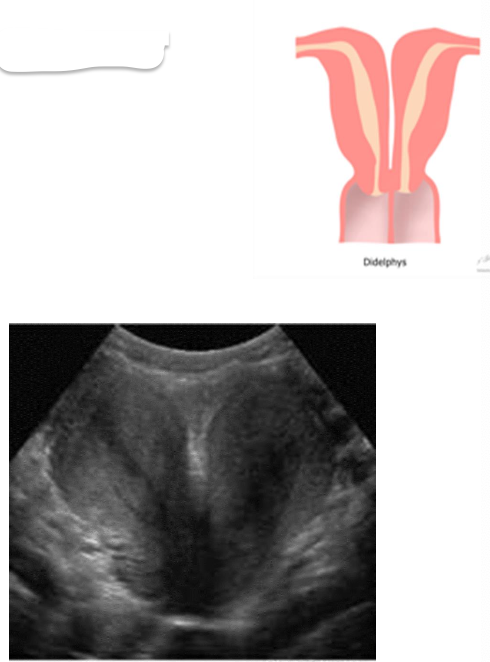

– Double vaginas, cervixes, and uteri function separately

– The two uteri are at approximately a 450 angle to one another

Uterus Didelphus

– Improper fusion leads to two partially or completely separate bicornuate uterine cavities.

– The uterus is heart-shaped

– Most common congenital uterine anomaly.

Bicornuate uterus

This is?

Bicornuate Uterus